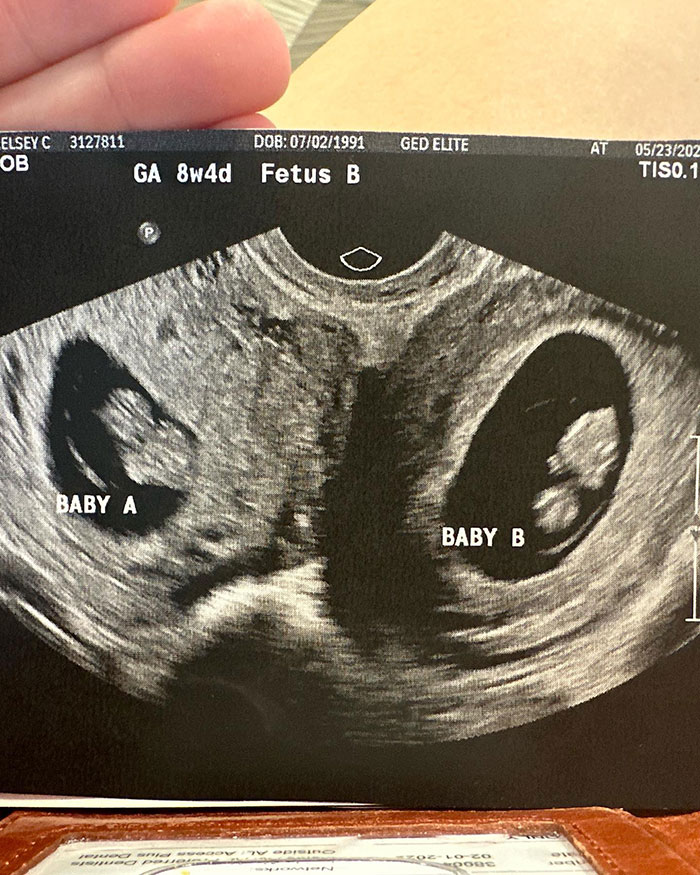

Kelsey Hatcher has a rare condition where she lives with a double uterus, expecting a child in each of the organs.

The expecting mom from Alabama, USA, was in fact born with two functional uteri that each have their own cervix.

Kelsey Hatcher is expecting two girls, pregnant in two sets of uterus, a rare condition she was born with

Upon discovering her pregnancy last spring, followed by a first ultrasound, Kelsey shared the amazing news that she was not only pregnant but expecting babies in both organs, with her husband Caleb.

As a result of the girls each growing in their own uterus with their own placenta, the specialists still speculate whether the babies will be twins or siblings.